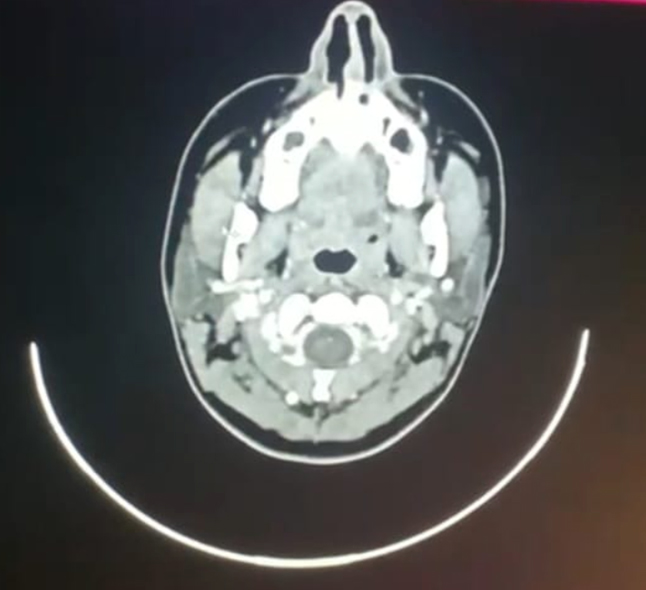

Fine needle aspiration cytology report of neck mass revealed granulomatous lymphadenitis and suggested excision of lymphnode for further assessment. USG neck shows well defined heterogeneous hypoechoic lesion in the left side of neck suggestive of schwannoma. Computed Tomography scan of neck showed a well defined fusiform heterogeneously enhancing lesion measuring 43x26x17 mm with cystic area noted in left level IV abutting left IJV medially and sternocleidomastoid anteromedially. There is non enhancing areas within the lesion – S/O necrosis with no evidence of calcification/sinus formation.

Figure 2. CT neck sagittal and axial view